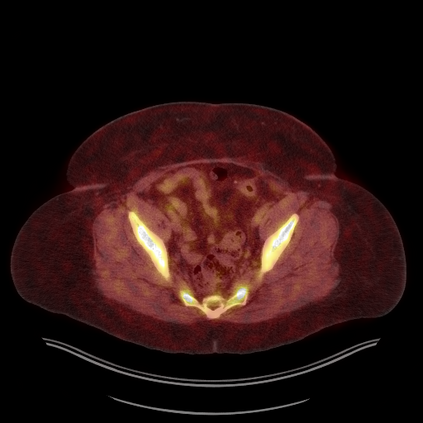

Medical images play a crucial role in assisting diagnosis, remote consultation, and academic research. However, during the transmission and sharing process, they face serious risks of copyright ownership and content tampering. Therefore, protecting medical images is of great importance. As an effective means of image copyright protection, zero-watermarking technology focuses on constructing watermarks without modifying the original carrier by extracting its stable features, which provides an ideal approach for protecting medical images. This paper aims to propose a fragile zero-watermarking model based on dual quaternion matrix decomposition, which utilizes the operational relationship between the standard part and the dual part of dual quaternions to correlate the original carrier image with the watermark image, and generates zero-watermarking information based on the characteristics of dual quaternion matrix decomposition, ultimately achieving copyright protection and content tampering detection for medical images.